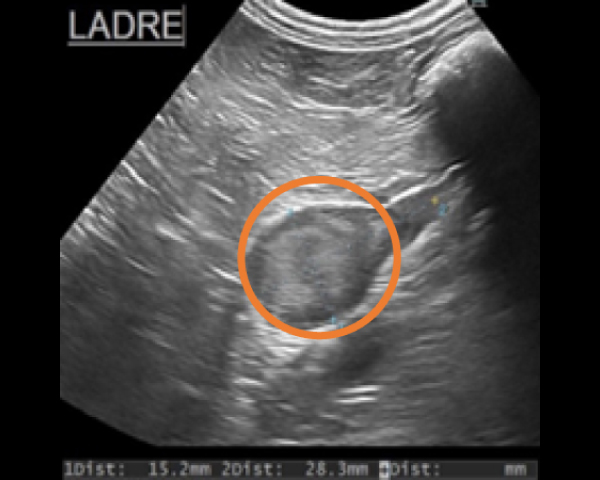

超音波にて副腎腫瘤を確認

造影CT検査にて腫瘤の浸潤を評価